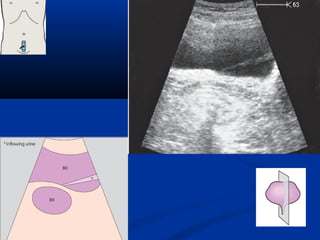

Khaûo saùt sieâu aâmKhaûo saùt sieâu aâm

Khaûo saùt sieâuaâmKhaûo saùt sieâu aâm Phuï thuoäc:Phuï thuoäc: - Theå traïng ngöôøi beänhTheå traïng ngöôøi beänh - Kinh nghieäm ngöôøi laøm sieâu aâmKinh nghieäm ngöôøi laøm sieâu aâm - Loaïi thieát bòLoaïi thieát bò Yeâu caàu:Yeâu caàu: - Nhòn ñoùi ít nhaát 6 giôø ñeå haïn cheáNhòn ñoùi ít nhaát 6 giôø ñeå haïn cheá hôi ruoäthôi ruoät - Baøng quang caêng vöøa phaûiBaøng quang caêng vöøa phaûi